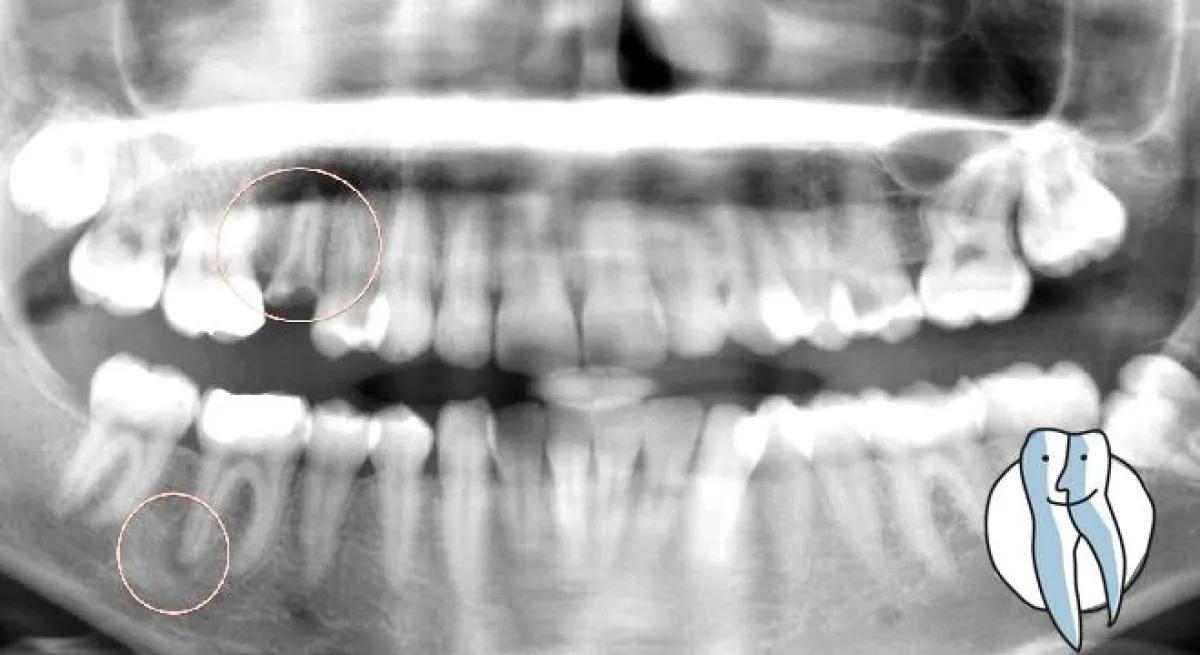

Der abgestorbene Zahn fällt auch nicht zwangsläufig aus, häufig merkt der Betroffene gar nichts am Zahn. Es kommt zu einer leichten Aufbissempfindlichkeit, zu einer gesteigerten heiss/kalt Empfindlichkeit. Unser Tip ist es daher auch bei leichten Beschwerden diesen Zahn kontrollieren zu lassen. Oft bringt ein Röntgenbild eine Entzündung an der Wurzelspitze zutage.